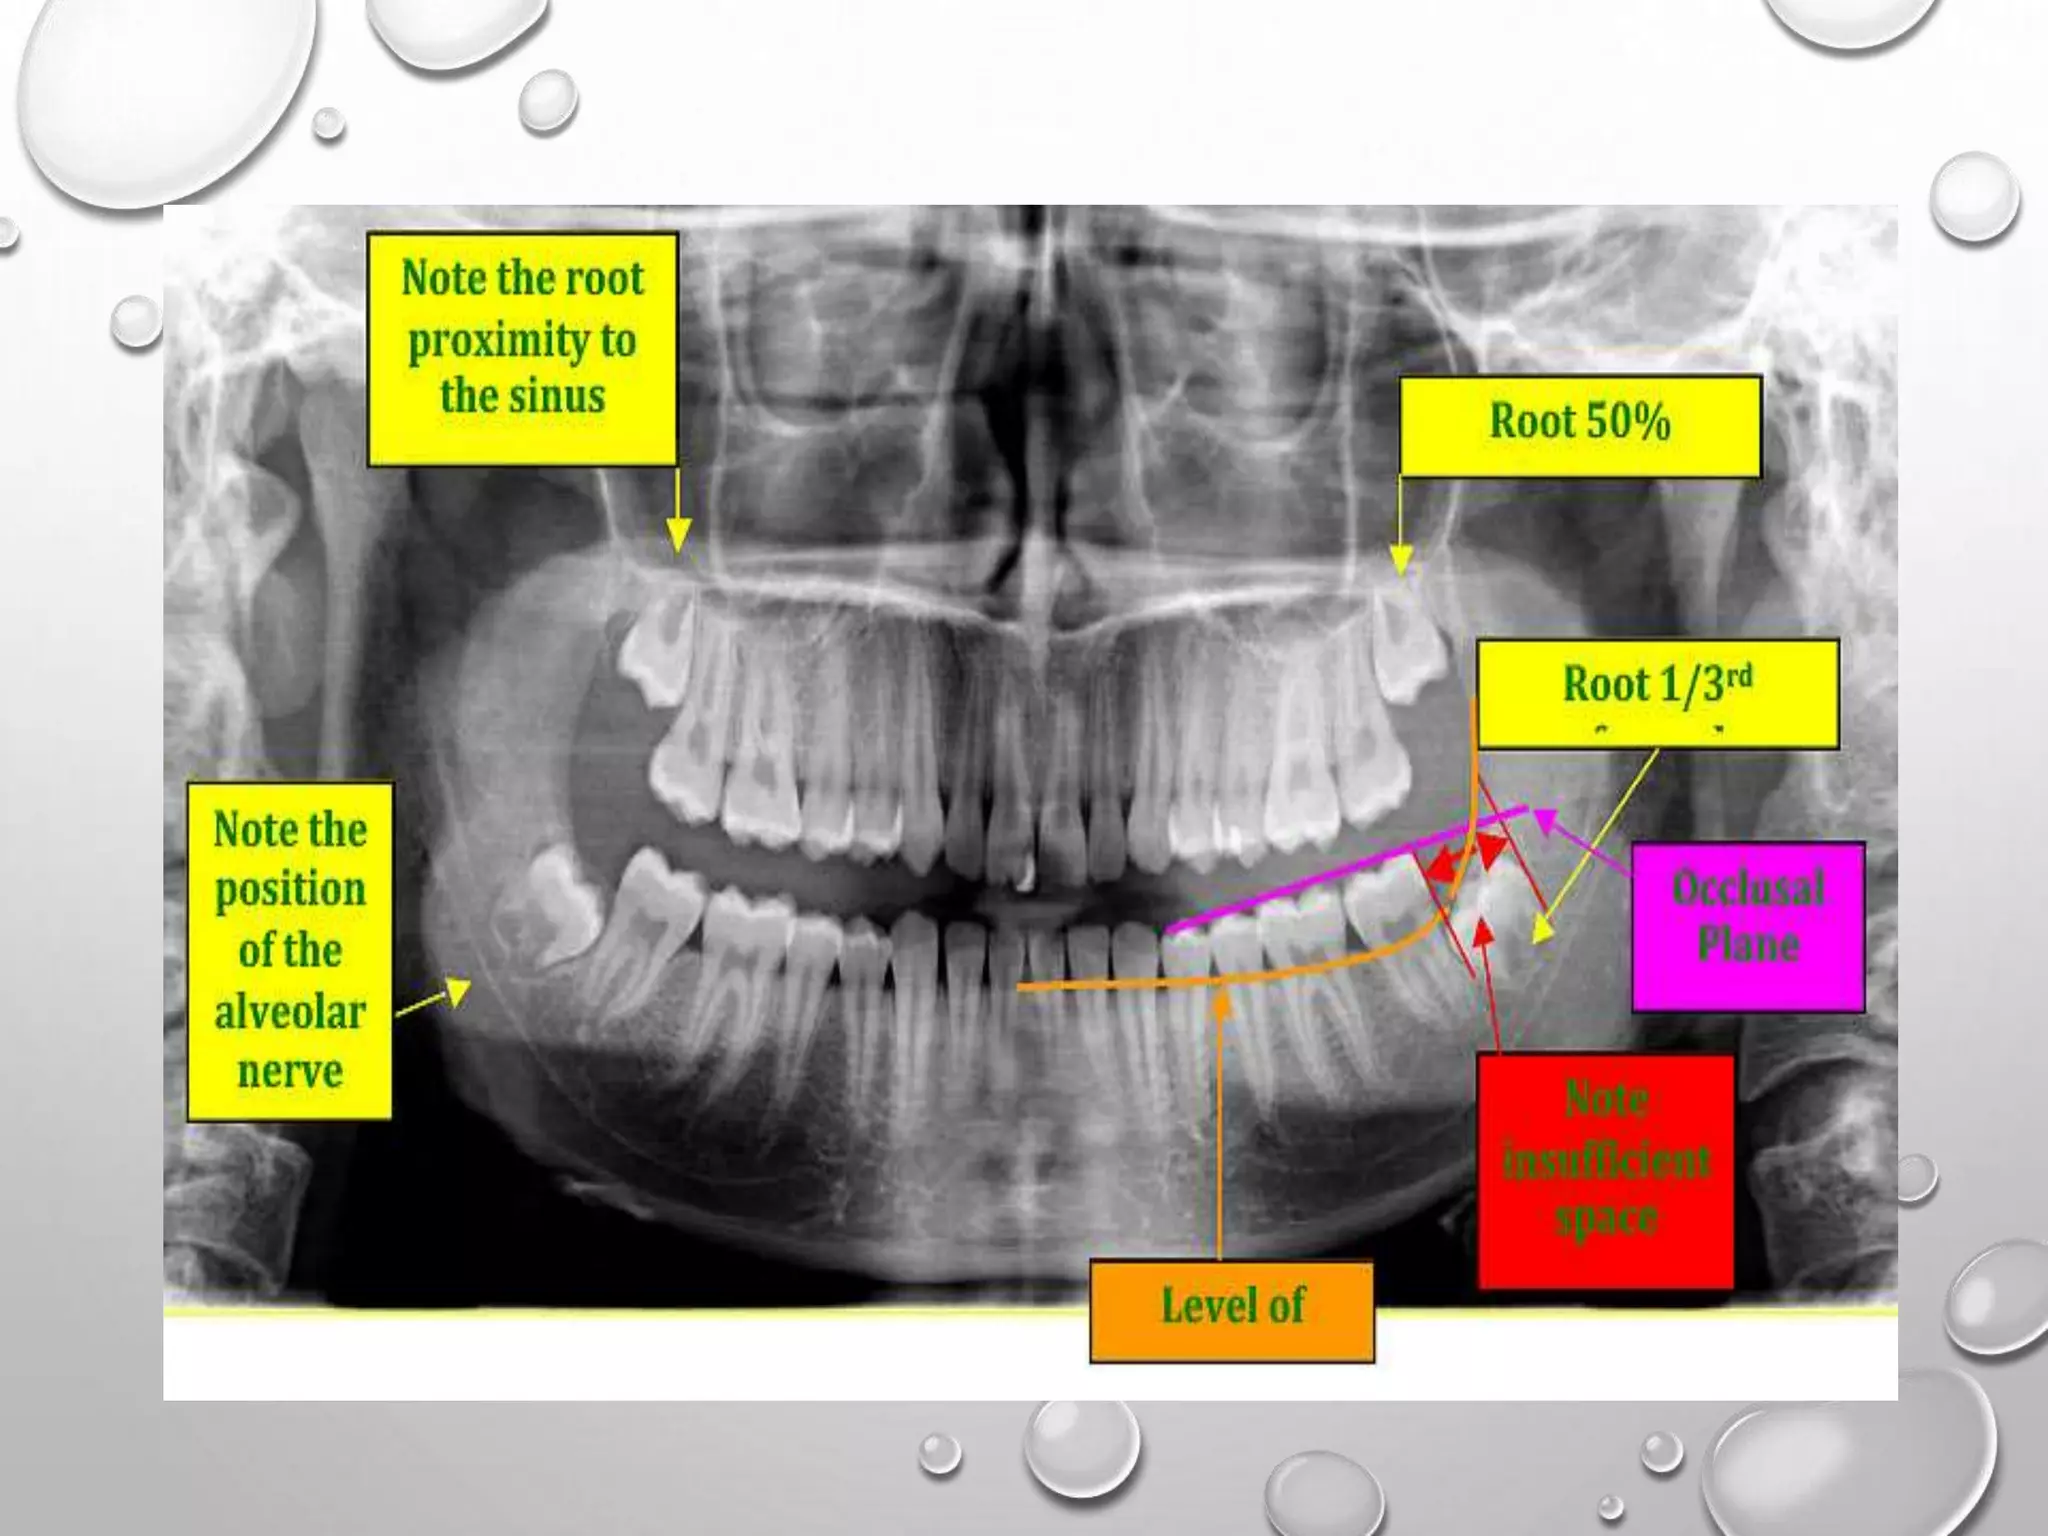

THE PANORAMIC RADIOGRAPH PROVIDES

INFORMATION ON THE NUMBER OF TEETH

PRESENT, ERUPTION PROBLEMS, ROOT

FORM AND LENGTH, QUALITY OF

ALVEOLAR BONE AND OTHER

PATHOLOGICAL CONDITIONS. PANORAMIC

RADIOGRAPHS ARE ALSO OFTEN TAKEN

DURING TREATMENT TO EVALUATE THE

PARALLELISM OF THE ROOTS AND THE

PRESENCE OF ROOT RESORPTION OR

BLUNTING OF THE ROOT APICES.